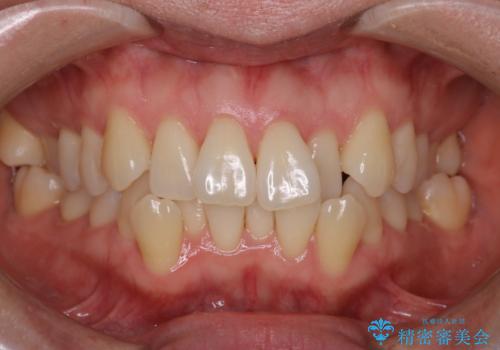

【抜歯ケース】前歯のガタガタをインビザラインで治療

- 前歯のガタガタを主訴に来院されました。

抜歯が必要なケースでしたが、インビザラインでの治療を希望されワイヤーを使用せずに治療を完了しております。